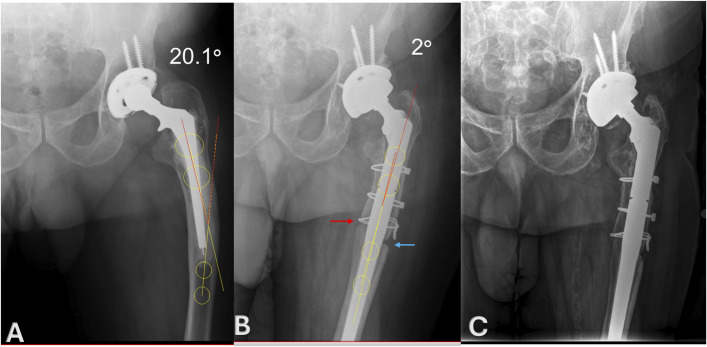

Results: All patients had preoperative varus femoral deformity (mean 16.3° ± 5.7°). The mean postoperative alignment was 4.3 ± 1.6° varus achieving an average correction of 12° (95% CI -15.7 to -8.3, p < 0.0001). Both the ETO and the medial corticotomy consolidated in 10 of 11 patients (91%) with available 1-year radiographs at a mean of 11 ± 7.7 months. The mean HHS improved significantly from 42 preoperatively to 82 at 5-year follow-up (p = 0.0002). Complications related to the ETO and corticotomy occurred in 4 patients (30%), including 1 intraoperative fracture, 1 postoperative greater trochanteric fracture, 1 nonunion of the medial corticotomy, and 1 postoperative wound-hematoma. All femoral components remained well fixed at final follow-up.

Abstract Image